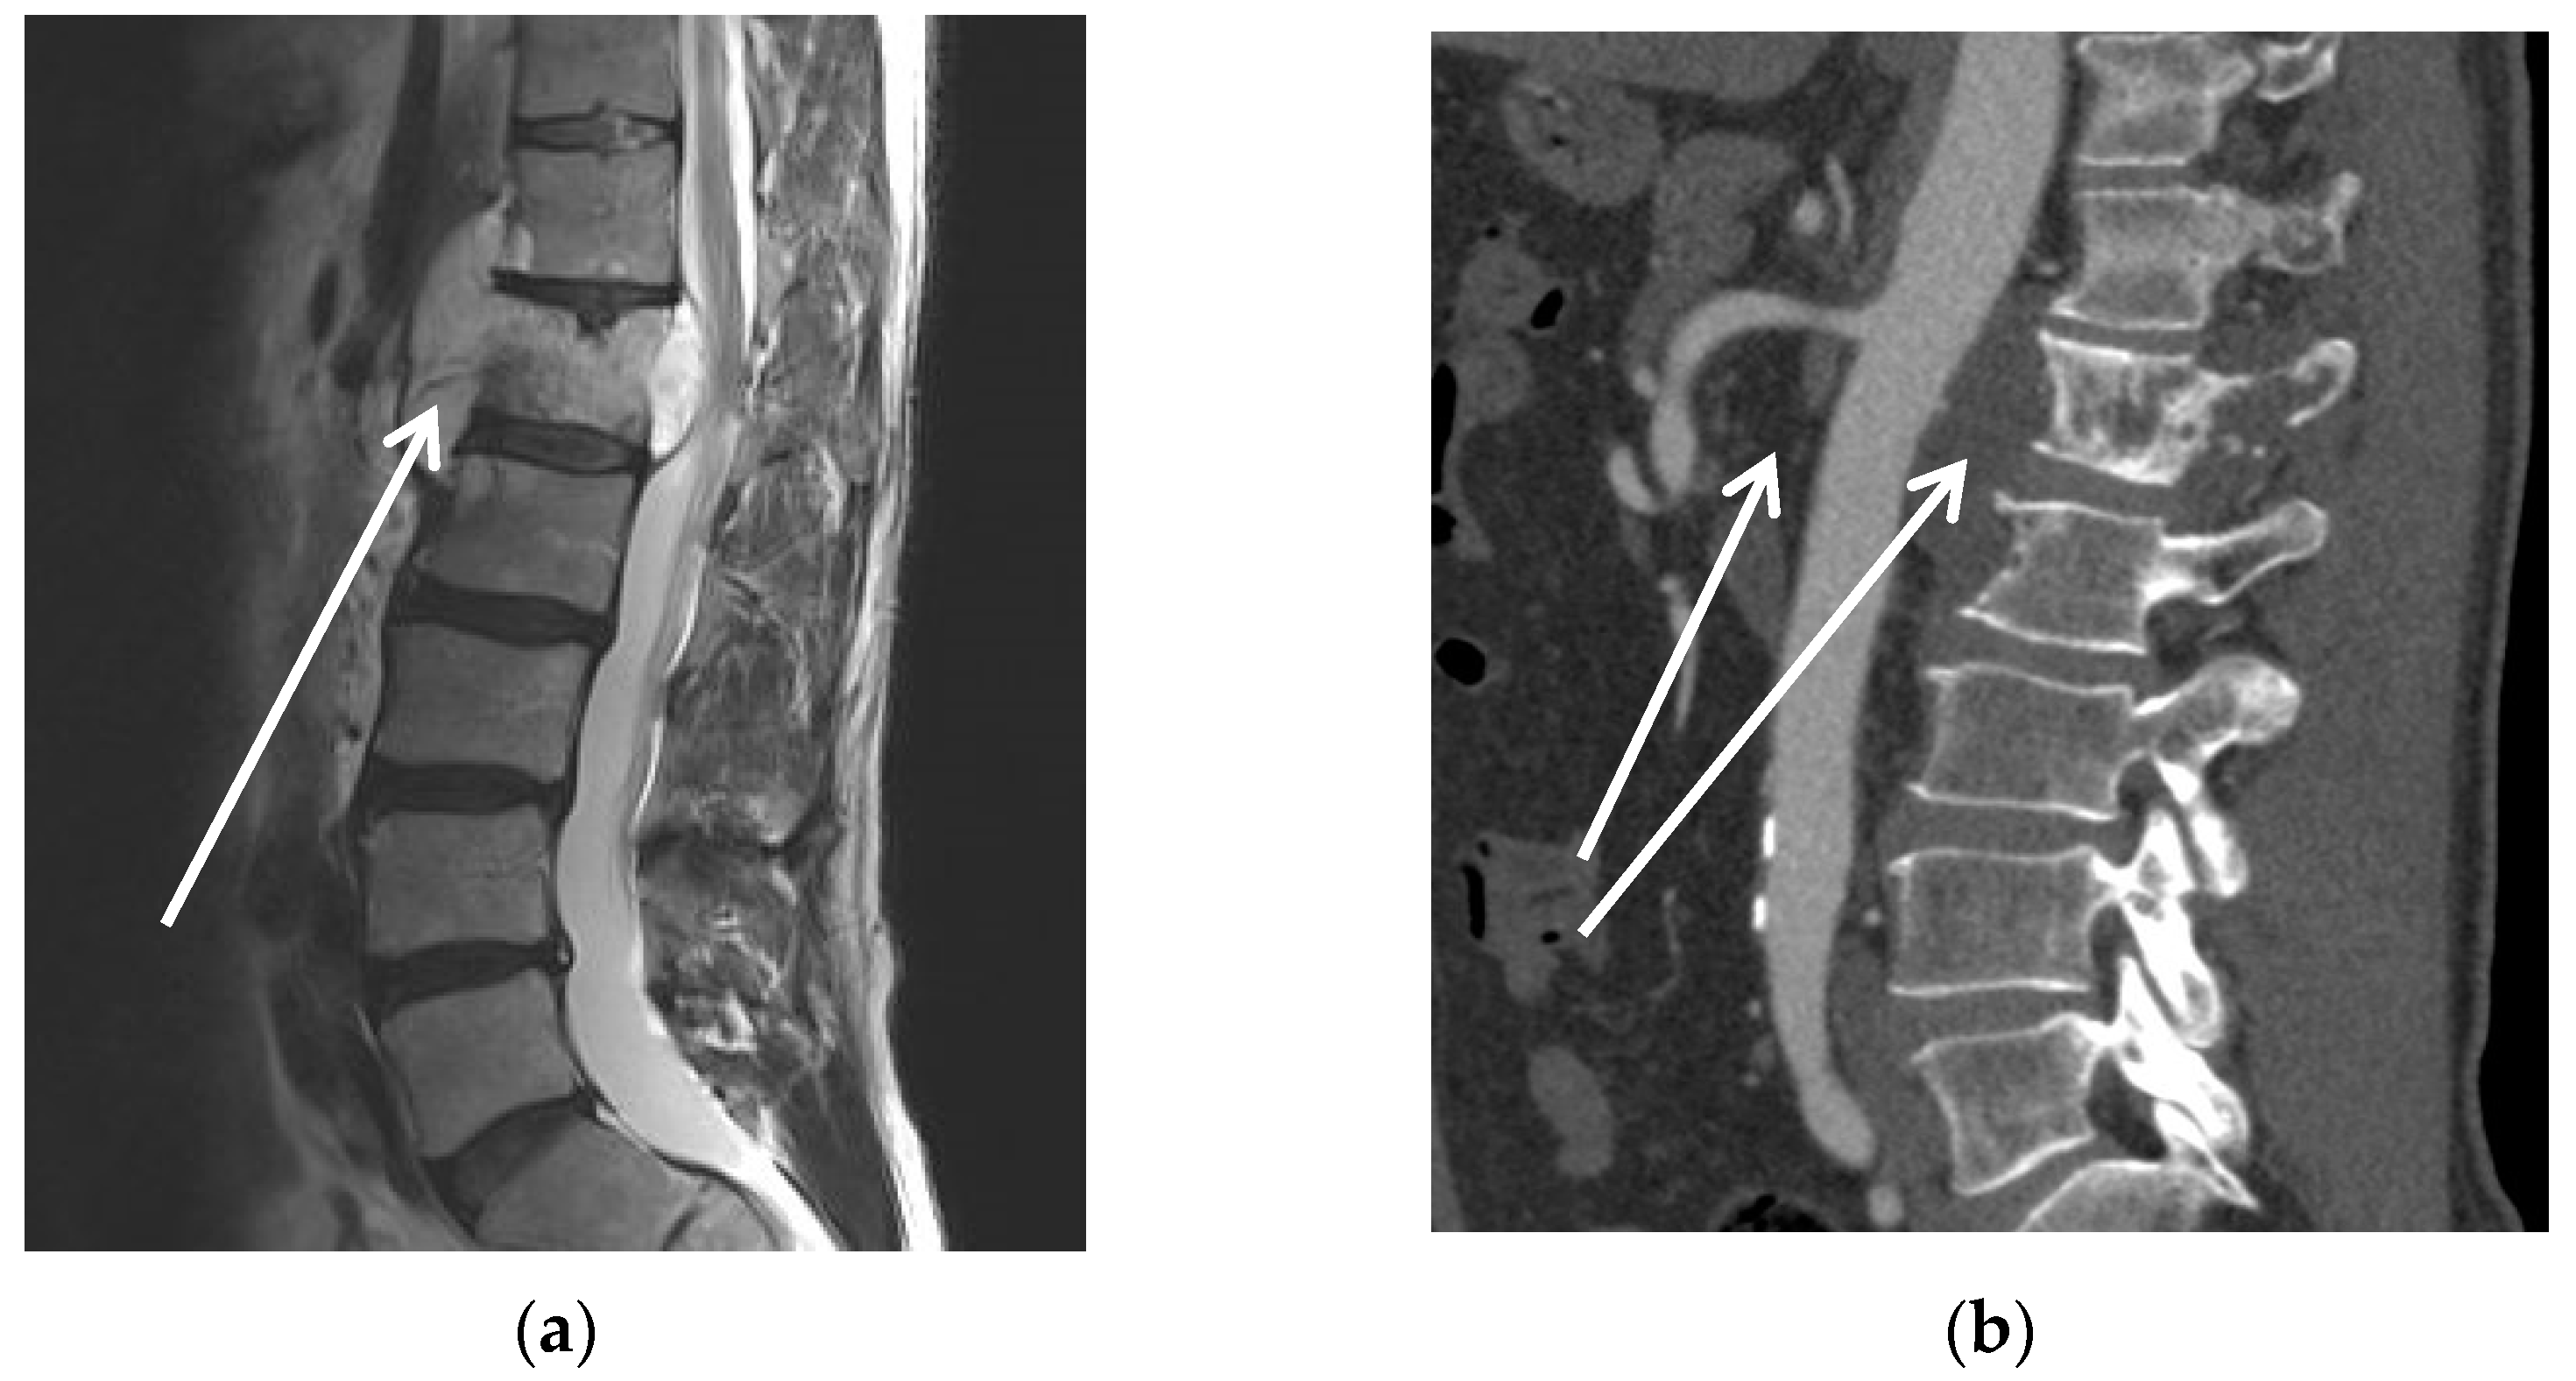

| 3 | m | 56 | Chordoma L1 | Spinal compression with impending paraplegia | Yes, proton therapy (50 Gy) | No | 1 | I |

| 4 | m | 41 | Retro-peritoneal rhabdoid sarcoma | hydronephrosis; patient’s wish for curative resection | Yes, proton therapy (50 Gy) | Yes | 0 | II |